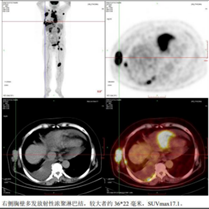

2024年11月21日至2025年1月22日,行西达本胺联合R-CHOP方案(利妥昔单抗375mg/m² d0,环磷酰胺750mg/m² d1,表柔比星90mg/m² d1,长春新碱2mg/m² d1,泼尼松100mg d1-5,西达本胺20mg d1/4/8/11)治疗4周期,同时予戈舍瑞林缓释植入剂进行生育保护。2025年2月12日PET-CT复查示原病灶消失,右扁桃体代谢不高,Deauville评分1分,疗效评估达完全缓解(CR)。

图片2025-02-12 PET-CT检查提示达完全缓解